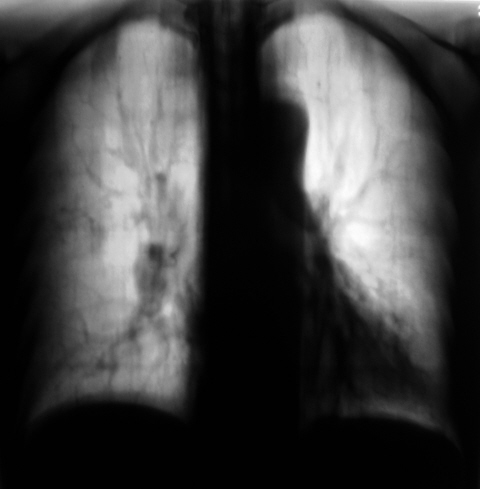

Пневмосклероз средней доли? Не ясна четкая сосудистая косая тень из синуса к корню

В проекции ствола правого корня округлый дефект выполнения. это что - сумация тени бронха? или что другое? Не совсем понятно.

Сдаюсь. Дополнительных теней, полицикличности не вижу. Может, просто крупный диаметр ветки легочной. Я бы сделала боковую томографию для уточнения структуры корня. Неоднородность за счет кальцинатов. В-общем, и динамику, и предыдущие ФЛГ посмотреть бы, но это от того, что просто не знаю.